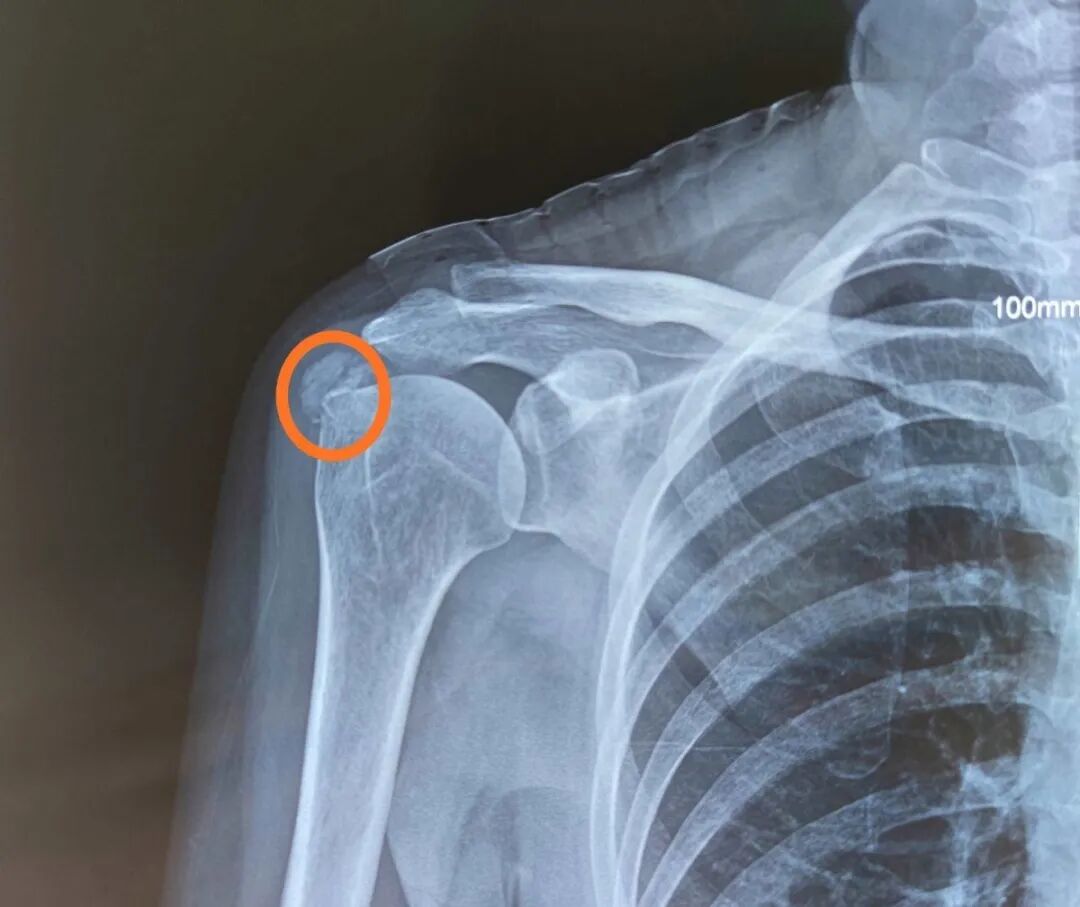

术后九个月未愈合 冲击波治疗后二个月

按骨折的部位和类型,经过治疗后,未能在平均时间内愈合,骨折断端仍未出现骨折连接,称为骨折延迟愈合。ESWT 具有成骨作用,在治疗骨折延迟愈合方面应用越来越广泛,治疗胫骨、跖骨、股骨等骨折延迟愈合时,总体有效率 70%~90%.